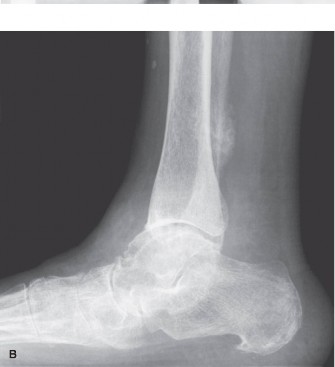

The hindfoot comprises the talus and calcaneus. Crucial radiographic parameters include:

* Talar declination angle and calcaneal pitch angle: Indicating arch height.

* Böhler's angle and Gissane's angle: Critical for evaluating calcaneal fractures.

* Subtalar joint alignment: Best assessed on hindfoot alignment views or CT, revealing varus or valgus deformities.

* Calcaneal fractures: Displaced intra-articular fractures (e.g., depressed Böhler's angle), significant subtalar joint involvement.

| Calcaneal Fractures | Displaced intra-articular fractures (e.g., Böhler's angle <20° or depressed posterior facet), significant subtalar incongruity. | Extra-articular, non-displaced intra-articular, or stable posterior facet fractures. |